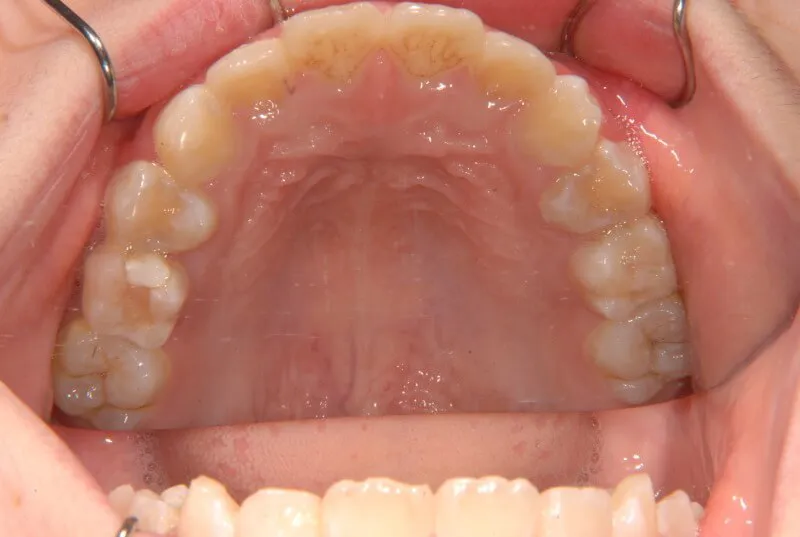

| 初診時年齢 | 小学校1年生(女性) | 主訴 | 受け口 | ||

| 診断名 | 叢生・反対咬合 | 装置名 | 拡大床 | ||

| 抜歯の有無 | 非抜歯 | 治療期間・通院回数 | 2年7ヶ月・21回 | ||

| 費用 | 481,890円(税込) | 費用内訳 | 相談料:1,050円 検査料:46,200円 施術料:210, 000円 装置料:105,000円 保定装置料:52,500円 調整料:3,150円×10回=31,500円 以上 消費税率5% / 調整料:3,240円×11回=35,640円 以上 消費税率8% | ブラケット・ ワイヤー |

付けずに治した |

| 特徴 |

固い食べ物が嫌い 乳歯列が綺麗に並んでいる ゆがんで生えている よく噛まないで飲み込む |

| 状態 |

永久歯が生える隙間がない(叢生) 受け口(口元が出ている/下顎前突/反対咬合) |

| リスク・副作用 |

矯正歯科治療に伴う一般的なリスク・副作用

|